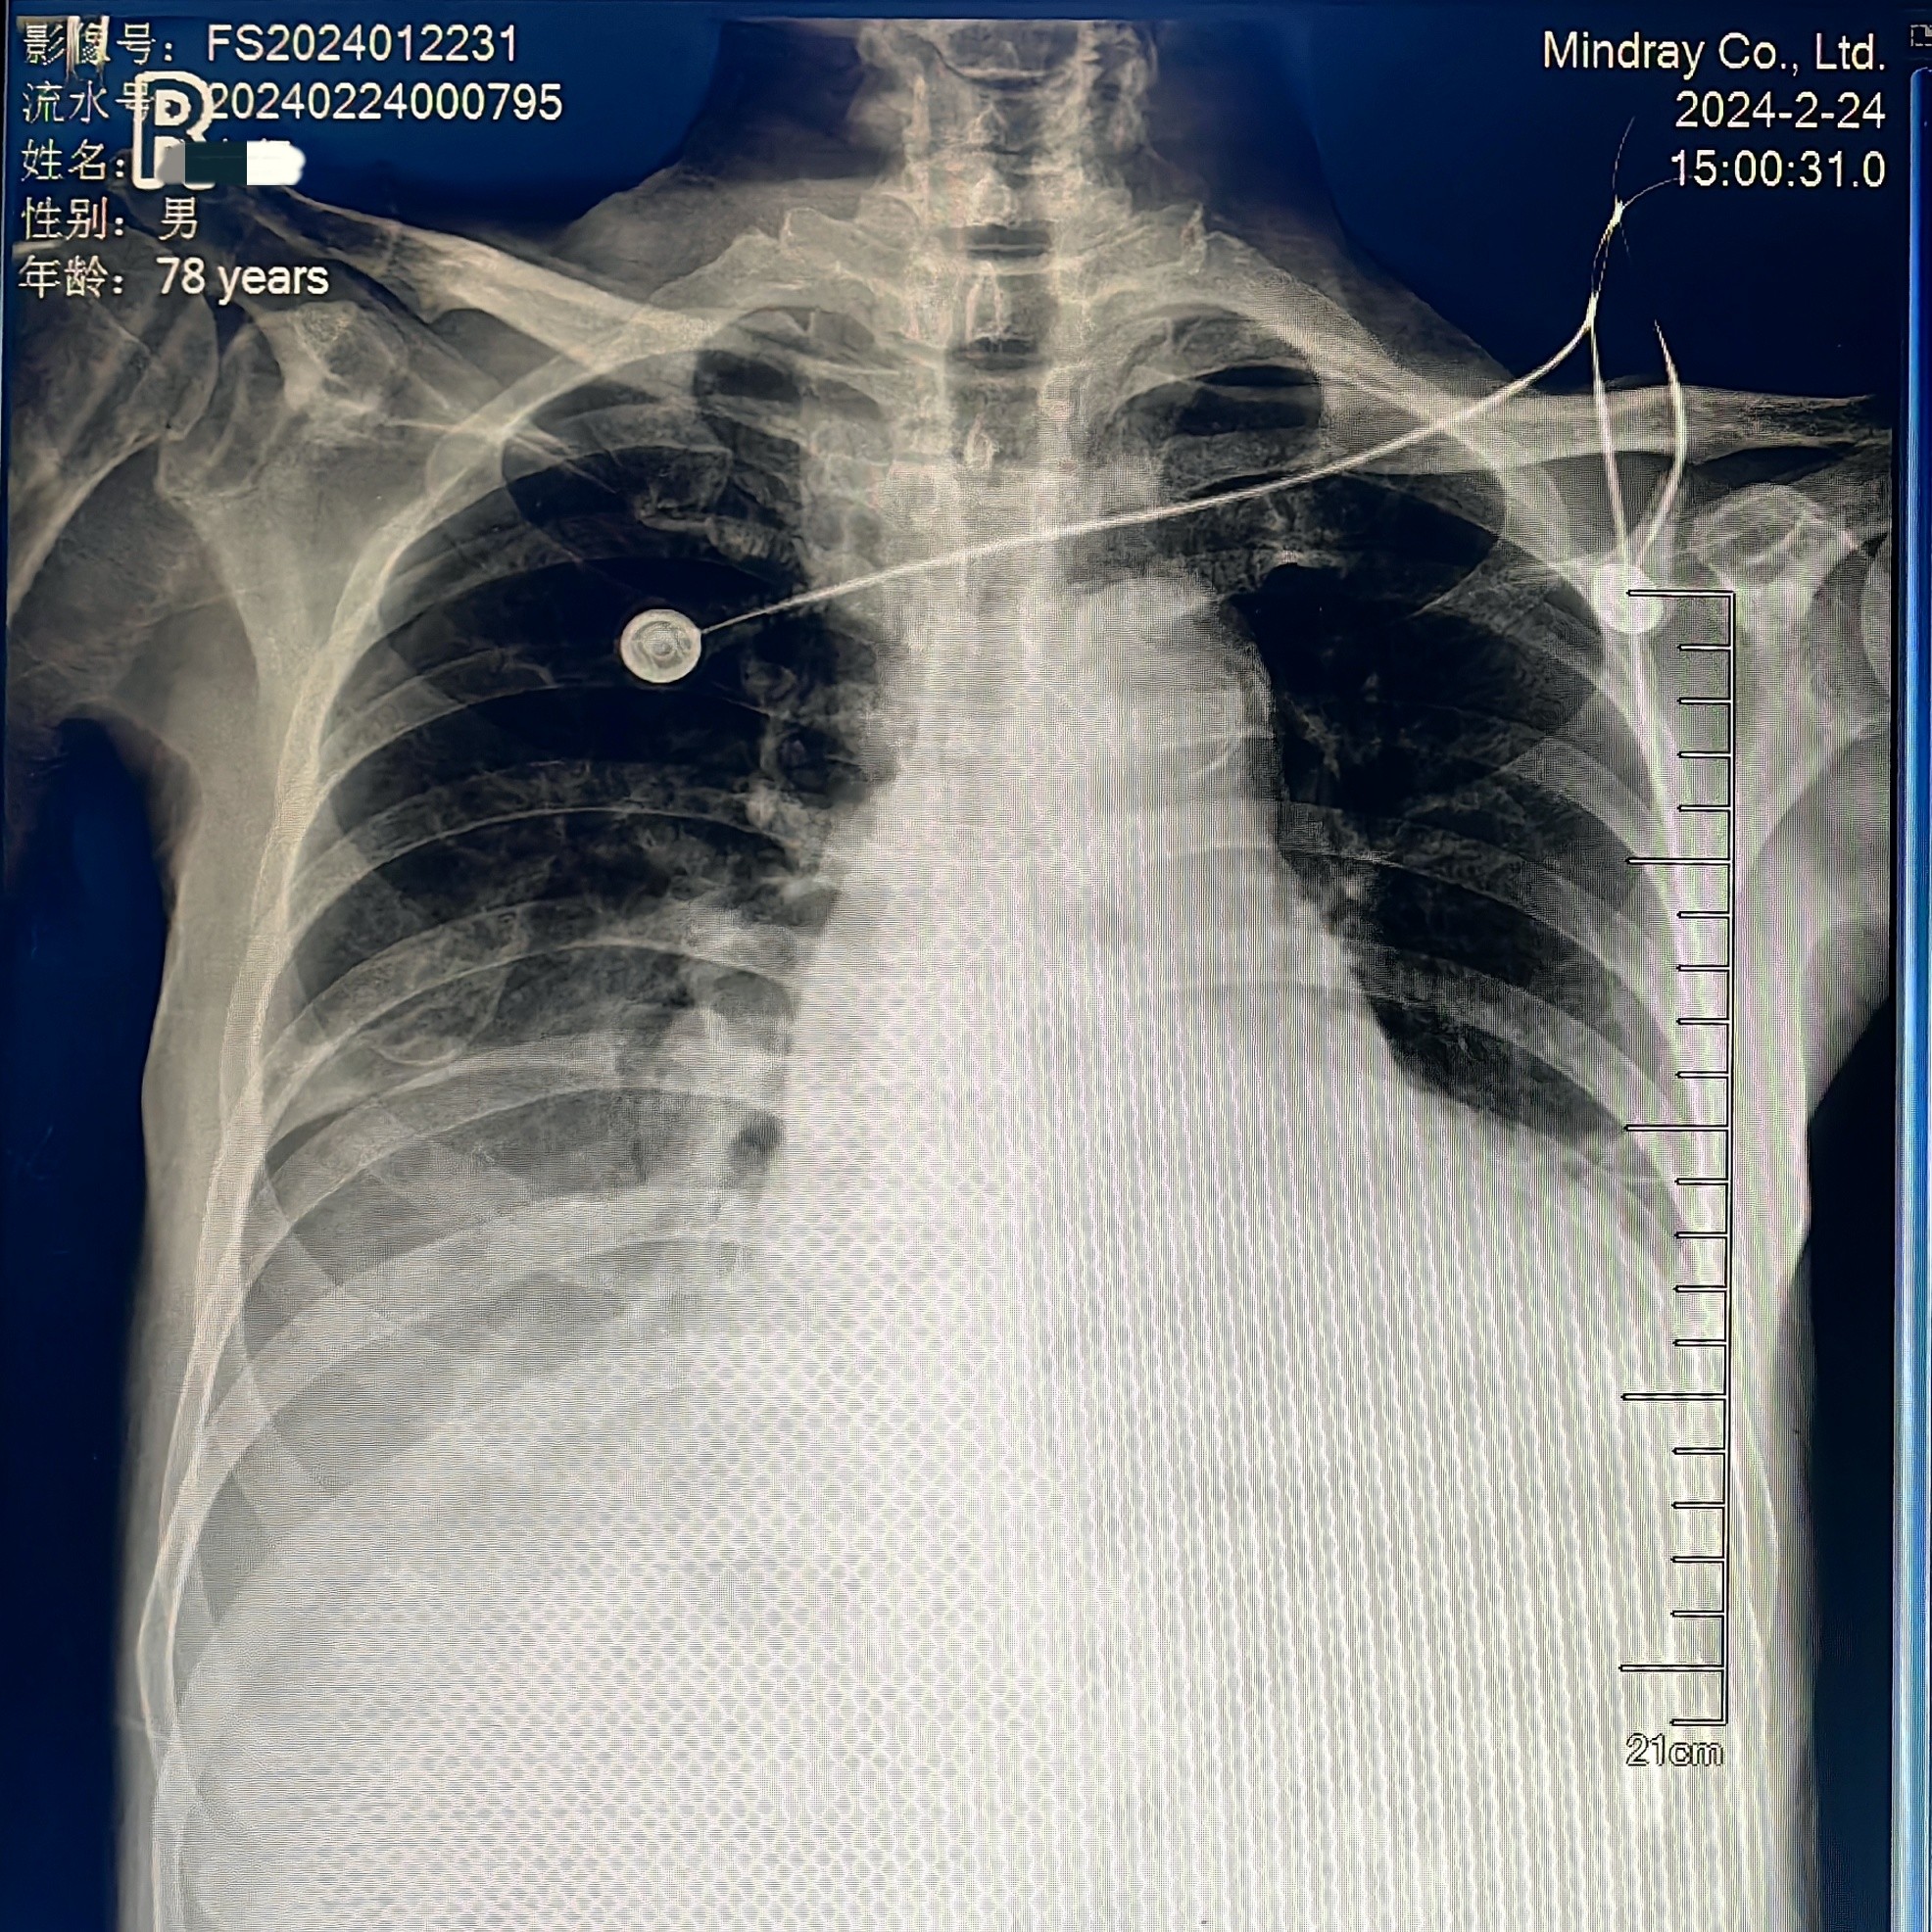

图片2:入院时胸片心影扩大、肺部感染、胸腔积液

好景不长,外院刚出院不久,老唐又因“心衰”发作于2月21日入住医院心血管内科,床旁心脏超声提示:主动脉瓣重度关闭不全,合并有二尖瓣中-重度关闭不全,三尖瓣中-重度关闭不全,升主动脉增宽。动脉血气分析提示II型呼吸衰竭、高碳酸血症、高钾血症、乳酸酸中毒等,病情十分危重,患者胸闷、气促心衰症状明显,正常呼吸都费劲,不能平躺休息,意识状态迷糊,无尿,经药物治疗后症状缓解不明显,随时有可能出现呼吸心脏骤停,经重症医学科会诊后有紧急气管插管指征(有创呼吸机辅助呼吸),老唐此刻命悬一线!